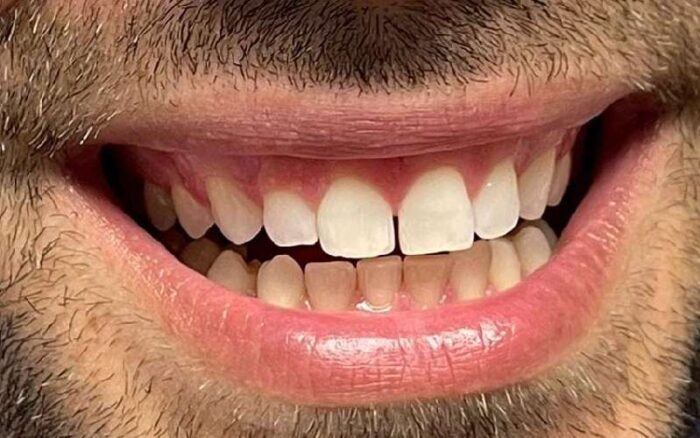

Lo Studio Dentistico Porro e Artusa opera con competenza e professionalità a Segrate da 25 anni. In questa sezione ti presentiamo alcuni dei molteplici casi clinici che abbiamo trattato.

Vedrai la situazione di partenza e il risultato ottenuto attraverso i nostri interventi. Se hai un problema alla bocca te lo risolveremo! Non esitare a chiederci un appuntamento, torna a sorridere.